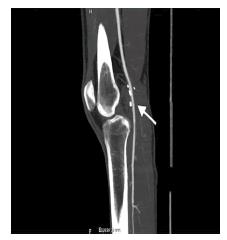

Con estos hallazgos, se planteó como primera posibilidad una enfermedad quística de la adventicia de la arteria poplítea, con estenosis crítica secundaria. Posteriormente, una resonancia magnética (RM) de rodilla demostró alteraciones similares (figura 2). En la angiografía por RM de la región poplítea se observó, además, la zona de compresión y ausencia de flujo segmentario en la arteria poplítea (figura 3).

La angiografía por sustracción digital se ha considerado el método de referencia para su evaluación 9,10; sin embargo, actualmente ha sido reemplazada por la RM y la angio-RM 10 que, además de demostrar la relación entre el quiste y la pared arterial, y la posible existencia de conexiones con la articulación adyacente 10, proporciona orientación para la planificación quirúrgica 8.

Los quistes pueden ser vistos en la pared de la arteria poplítea, pero también en sus ramas, como las arterias geniculadas 8. Los quistes se observan hiperintensos en imágenes ponderadas en T2 (T2WI), mientras que, en imágenes ponderadas en T1 (T1WI), presentan intensidad de señal variable según las diferencias en su contenido mucoide 8,10. En los quistes de mayor tamaño se pueden observar tabiques en su interior 8. En secuencias contrastadas con gadolinio, no presentan realce o solo captación en anillo 10.

Tanto la angiografía por sustracción digital como la angio-RM pueden demostrar una estenosis concéntrica (en forma de reloj de arena) o excéntrica (signo de la cimitarra) 8, aunque también pueden ser normales o evidenciar oclusión arterial completa no específica 8.